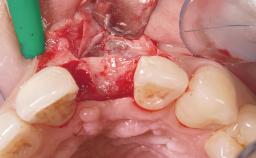

Immediate Placement of an Implant in a Maxillary Left Central Incisor Site

A 33-year-old female patient presented with an upper left central incisor that required extraction after a failed endodontic therapy. The tooth had been traumatized when the patient was a teenager and had undergone several endodontic treatments, including two apicectomy procedures. The patient was in good health and did not smoke. Clinical examination showed that the patient had a high lip line. In full smile, the gingival margins of the upper teeth were visible to the first molars. The gingival margins of central incisors 11 and 21 were only just showing. Examination of tooth 21 confirmed that the tooth was mobile and had hypererupted by 1 mm.

Placement Protocol Immediate implant placement

Tooth Site Maxillary incisor or canine

Socket Integrity Damage to one or more bone walls

Bone Volume Damage to one or more socket walls